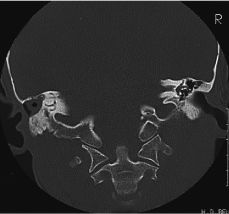

NEURORRADIOLOGÍA Utilidad y limitaciones de la TC en la patología inflamatoria del oído medio

Utility and limitations of CT in otitis media